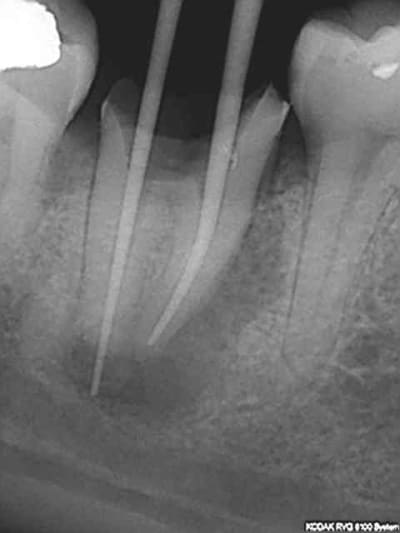

> @Chicot29: Tes endos sont superbes. Ce type de travail n'a aucune valeur pour

> santeclair et les autres guignols. Il n'y a que le prix, le prix, le prix. Tout

> le discours sur la qualité et le respect des normes de bonne pratique est de

> l'enfumage. Le but c'est de baisser le prix UN POINT C'EST TOUT. Il y a un

Ca c'était le cas de 14 h, voici le cas de 11h plus délicat. On verra ce que ca donne dans le temps ( finition au R40). C'est un peu creux en ce moment, heureusement qu'il y a des traitements réalisés conformément aux données acquises de la science à reprendre !)))))